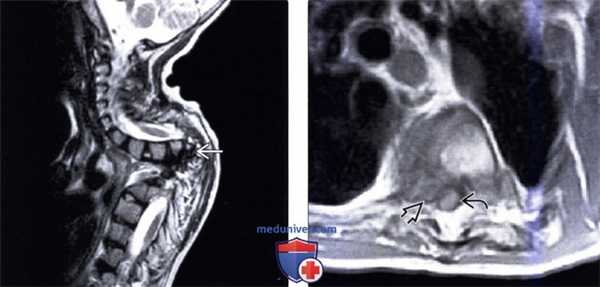

(Слева) На сагиттальной МРТ (Т2 ВИ) визуализируется маленький рудиментарный межпозвонковый диск на уровне С2-С3 (врожденное нарушение сегментации). Также определяется тяжелый стеноз позвоночного канала вследствие гипоплазии дуги С1.

(Справа) На корональной MPT (Т2 ВИ) у ребенка с врожденным нарушением сегментации С2-С3 определяется гипоплазия диспластического зубовидною отростка с наклоном его вправо. Слегка асимметричное поражение рудиментарною диска С2-С3 приводит к легкому сколиозу шейного отдела позвоночника.